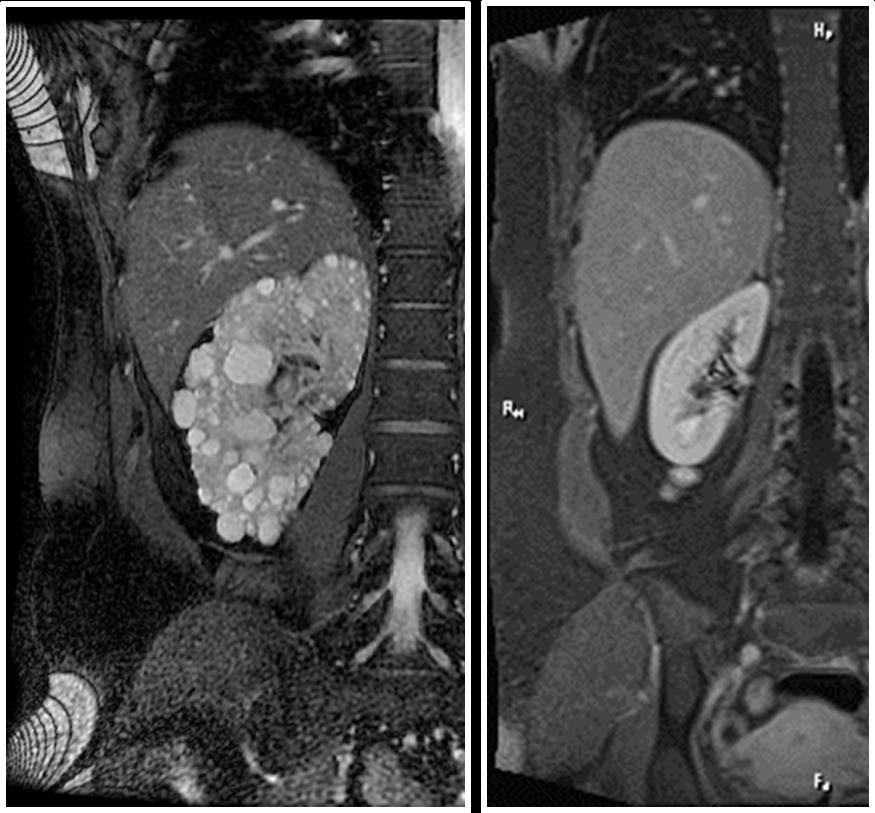

圖說:磁振造影下,左圖為多囊腎,右圖為正常腎臟。